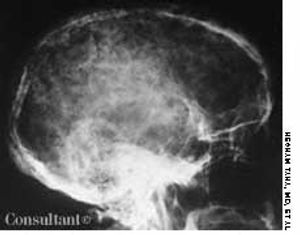

A 28-year-old woman reported that she was in good health before experiencing generalized weakness; exhaustion; and pain in her legs, shoulders, and back for the past 3 months. She also complained of shortness of breath with minimal activity, irregular menstrual periods, and occasional episodes of nose and gum bleeding.